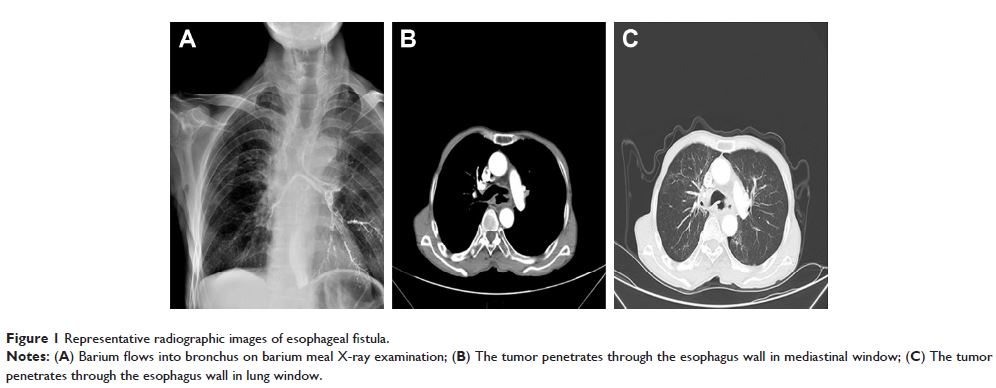

Case Report

- 作者:Hua Duan, Yanmei Peng, Huijuan Cui, Yuqin Qiu, Qiang Li, Jingyi Zhang, Wen Shen, Chenyao Sun, Chufan Luo

- 期刊:OncoTargets and Therapy